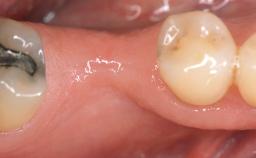

Periodontal Plastic Surgery and Prosthetic Procedures to Treat Peri-Implant Soft-Tissue Dehiscences

A 30-year-old woman was referred by her general dentist for evaluation of an esthetic complication related to previous implant treatment for congenitally missing maxillary lateral incisors. The patient’s chief complaint was the inadequate esthetic appearance of her smile. The case demonstrates the use of a combined approach to achieve optimal results. Two different flap designs - a tunnel technique and a coronally advanced flap - are employed based on the surgical objectives for the affected site.